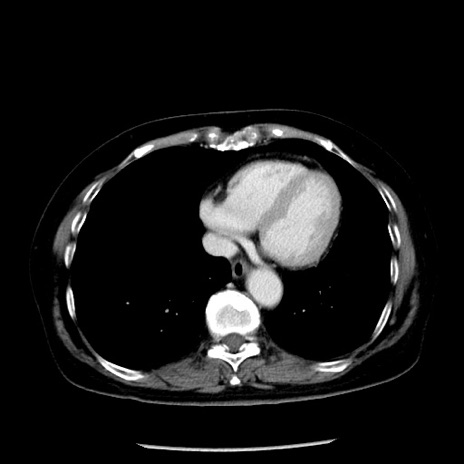

症例13(横断像)

【症例】70歳代女性

【主訴】腹痛、嘔吐

【現病歴】15時間程前(昨晩)より腹痛あり。今朝になっても症状の改善なく、嘔吐あり。腹痛も増悪あり、救急外来受診。

【既往歴】子宮癌全摘術後

【身体所見】意識清明、BP 121/72mmHg、P 74bpm、SpO2 100%(RA)、腹部:平坦・軟、腸雑音ほぼ聴取せず。下腹部・心窩部・臍左上に圧痛あり。反跳痛なし。

【データ】WBC 10600、CRP 0.15